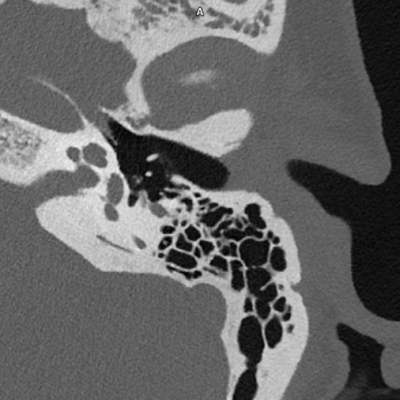

Innenohr

Vor allem bei sehr feinen Strukturen wie im Innenohr sind mittels Photon-Counting-CT detailreiche Darstellungen der Knochenstruktur möglich.